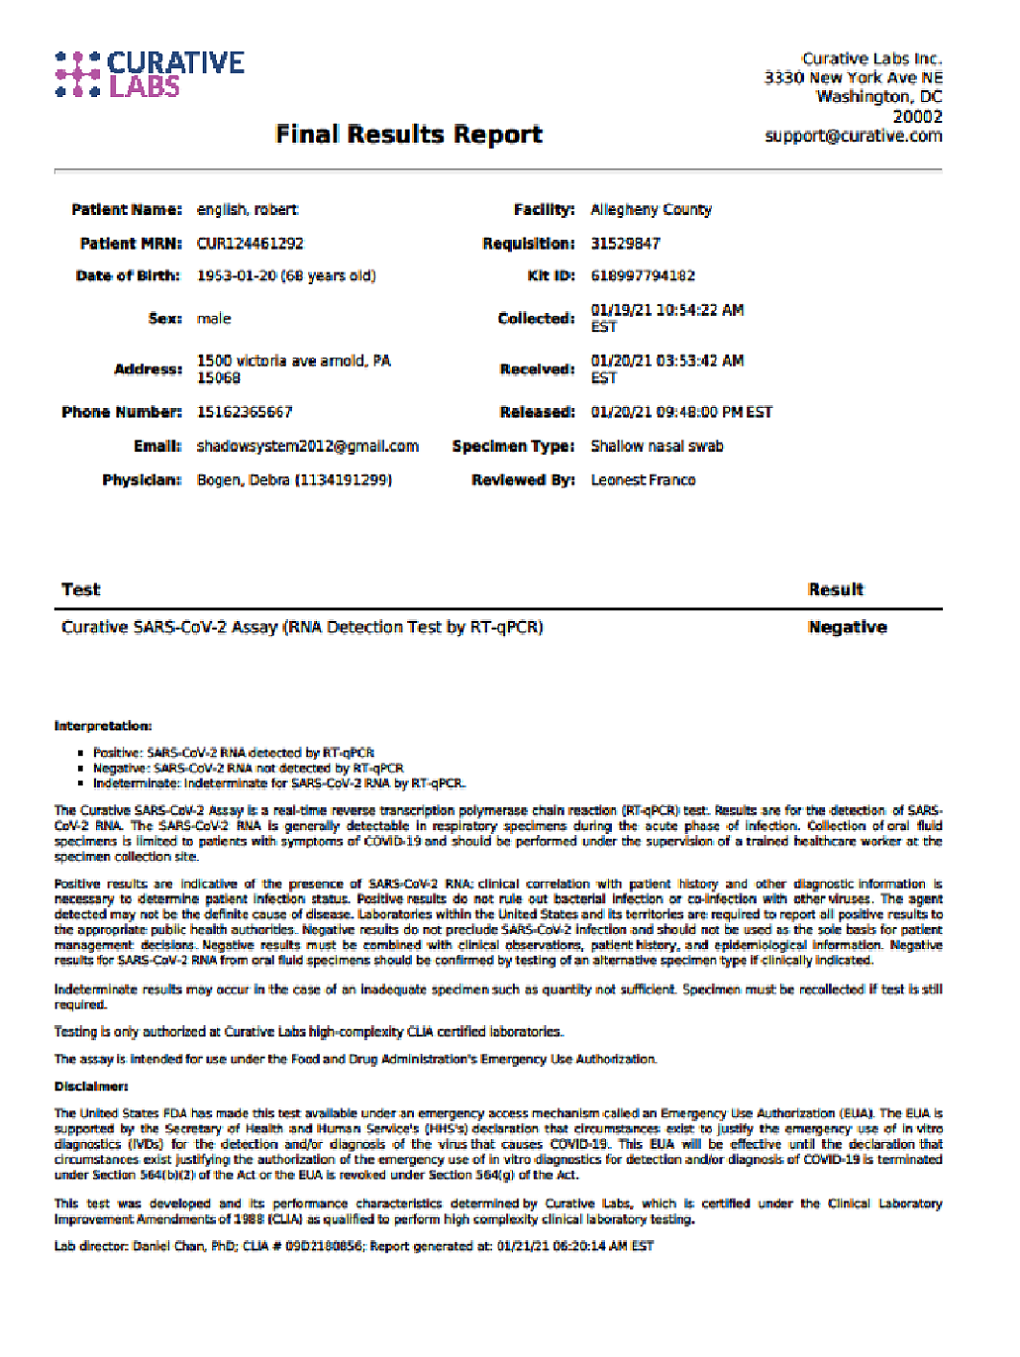

In late 2019 North Korea's Dictator threatened the President of these United States that he was sending the U.S. a Christmas Gift!

After launching several menicing rockets into the Sea of Japan a virus so infectious and deadly appeared. First in China, travelers infecting a global population in a matter of months. Noone thought anything about the actual origin, they just blamed the Chinese.

Nobody checked the the Weather Flow Paterns within the Jetstream in 2019.

DURING THE LAST YEAR I TOOK THE TIME TO SPEND WITH FAMILY. FRIENDS, SOME OF WHOM CONTRACTED COVID-19. SOME DIED AS A RESULT. FAMILY IS EVERYTHING SO I DID WHAT I COULD TO HELP THEM BY PAYING IT BACKWARD AND FOREWARD.